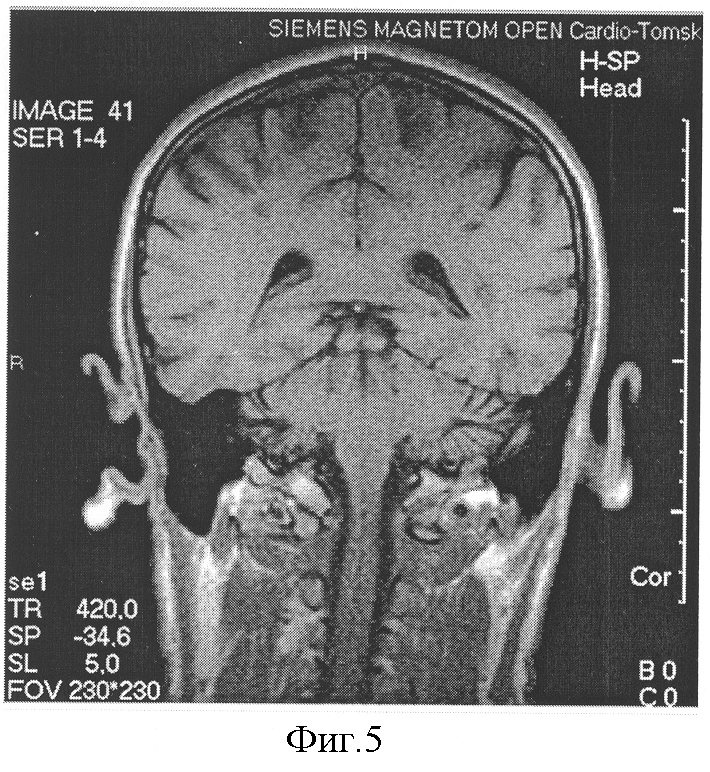

На фиг.5 изображено МРТ исследования головного мозга в после операционном периоде.

Послеоперационный период протекал без осложнений. Перед выпиской пациенту было выполнено контрольное исследование головного мозга на предмет выявления признаков нарушения мозгового кровообращения в области оперируемой артерии. Результаты МРТ представлены на фиг.5.: После одновременной коррекции стеноза ВСА справа и коронарного шунтирования на Т2 – взвешенной послеоперационной МРТ данных за повреждение мозга в области риска не выявлено